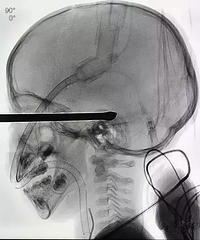

儿童安全问题不容小觑,小编今天又看到一条 孩子在家中不慎受重伤的新闻!!再次提醒家长:家中的利器一定要放好,不然一不小心就会造成惨祸。不小心从床上摔下男童被螺丝刀插入脑部 5月30日晚,深圳市儿童医院总值班接宝安区某医院转运电话,一名“头部锐器插入伤”患儿需紧急送至医院抢救,孩子病情危重,颅内情况不明确。 总值班接电话后,医方立即启动了